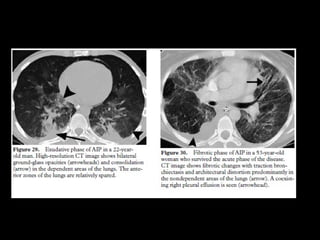

AIP

• Rápidamente progresiva

• Persona sana en días o semanas

• DAD de causa desconocida

• DD: SDRA

• Ventilación mecánica O2

• 50% mortalidad

Histología• DAD fase aguda exudativa, proliferativa y fibrótica.

• Edema,, proliferación fb y neumocito2, deposición de colágeno

AIP CT

• Vidrio esmerilado

• Simétrico, bilateral LI

• Consolidaciones

• Tardía hay distorsión, bq x tracción y

panalización

• DD: SDRA, COP, P jirovecii, edema hidrostático,

neumonía eosinofílica aguda, hemorragia alveolar

difusa, proteinosis alveolar.